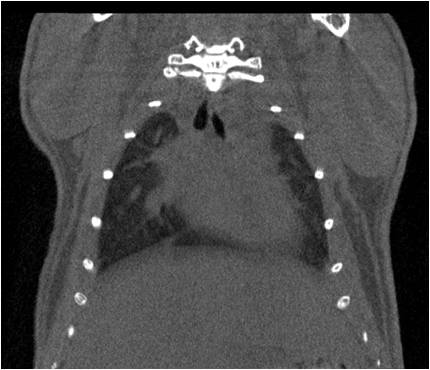

腫瘤血管生成

肺轉移

小鼠模式,22.5μm像素

正常

8天 14天

無造影劑注入 造影劑注入